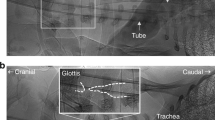

The neural control of respiratory airflow via the vocal fold is characterized by inspiratory abduction and postinspiratory (early expiratory) adduction causing decreases and increases in glottal resistance, respectively. The postinspiratory increase in glottal resistance plays a major role in braking the speed of expiratory airflow, to act against the high recoil pressure of the neonatal rat lung. In the present study, we investigated changes in upper airway patency during severe hypoxia in neonatal rats. We measured dynamic changes in subglottal pressure during normoxic and hypoxic conditions in an arterially perfused brainstem preparation in which we could control gas tensions accurately. Initially, hypoxia (5% O2, 5% CO2, and 90% nitrogen) produced an excitatory response in phrenic nerve activity accompanied by augmentation of both inspiratory-related glottal dilation and postinspiratory glottal constriction. Later, during the early stages of hypoxia-induced respiratory depression and initiation of gasping, we observed a massive reduction of the respiratory modulation of glottal resistance. In most preparations, this was transient and replaced by a paradoxic inspiratory-related glottal constriction. We propose that during severe hypoxia in the in situ preparation, paradoxic inspiratory glottal constriction can be observed during gasping, and this may impair ventilation despite the persistence of rhythmic contractions of the respiratory muscles. The latter is of clinical interest, because this may relate to the finding of cot death victims who died as a result of upper airway obstruction but without apparent apnea or rebreathing.